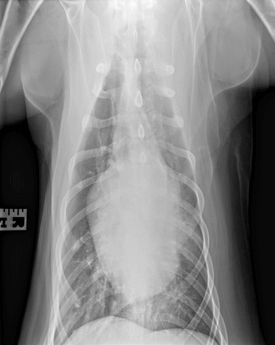

Chest x-rays did not have any significant findings.

Chest x-rays were repeated to monitor for signs of NCPE in case this was due to electrocution, and they revealed a “progressive ventral pulmonary infiltrate likely reflecting pneumonia” with a distribution not typical for NCPE.

The tongue swelling improved and nearly resolved after ~3 days. The ulcerations stopped progressing and remained static. Soren’s respiratory rate and effort were closely monitored, he remained eupneic on room air and did not require oxygen supplementation. He did have a productive cough. His energy level improved, and his personality became more playful and interactive. Due to persistent fever and cough on Day 6, chest x-rays were repeated and showed a more severe ventral alveolar infiltrate due to progressive pneumonia.

X-ray of a dog’s chest taken from a frontal view, showing lung and heart structure with some indications of possible infiltrates.